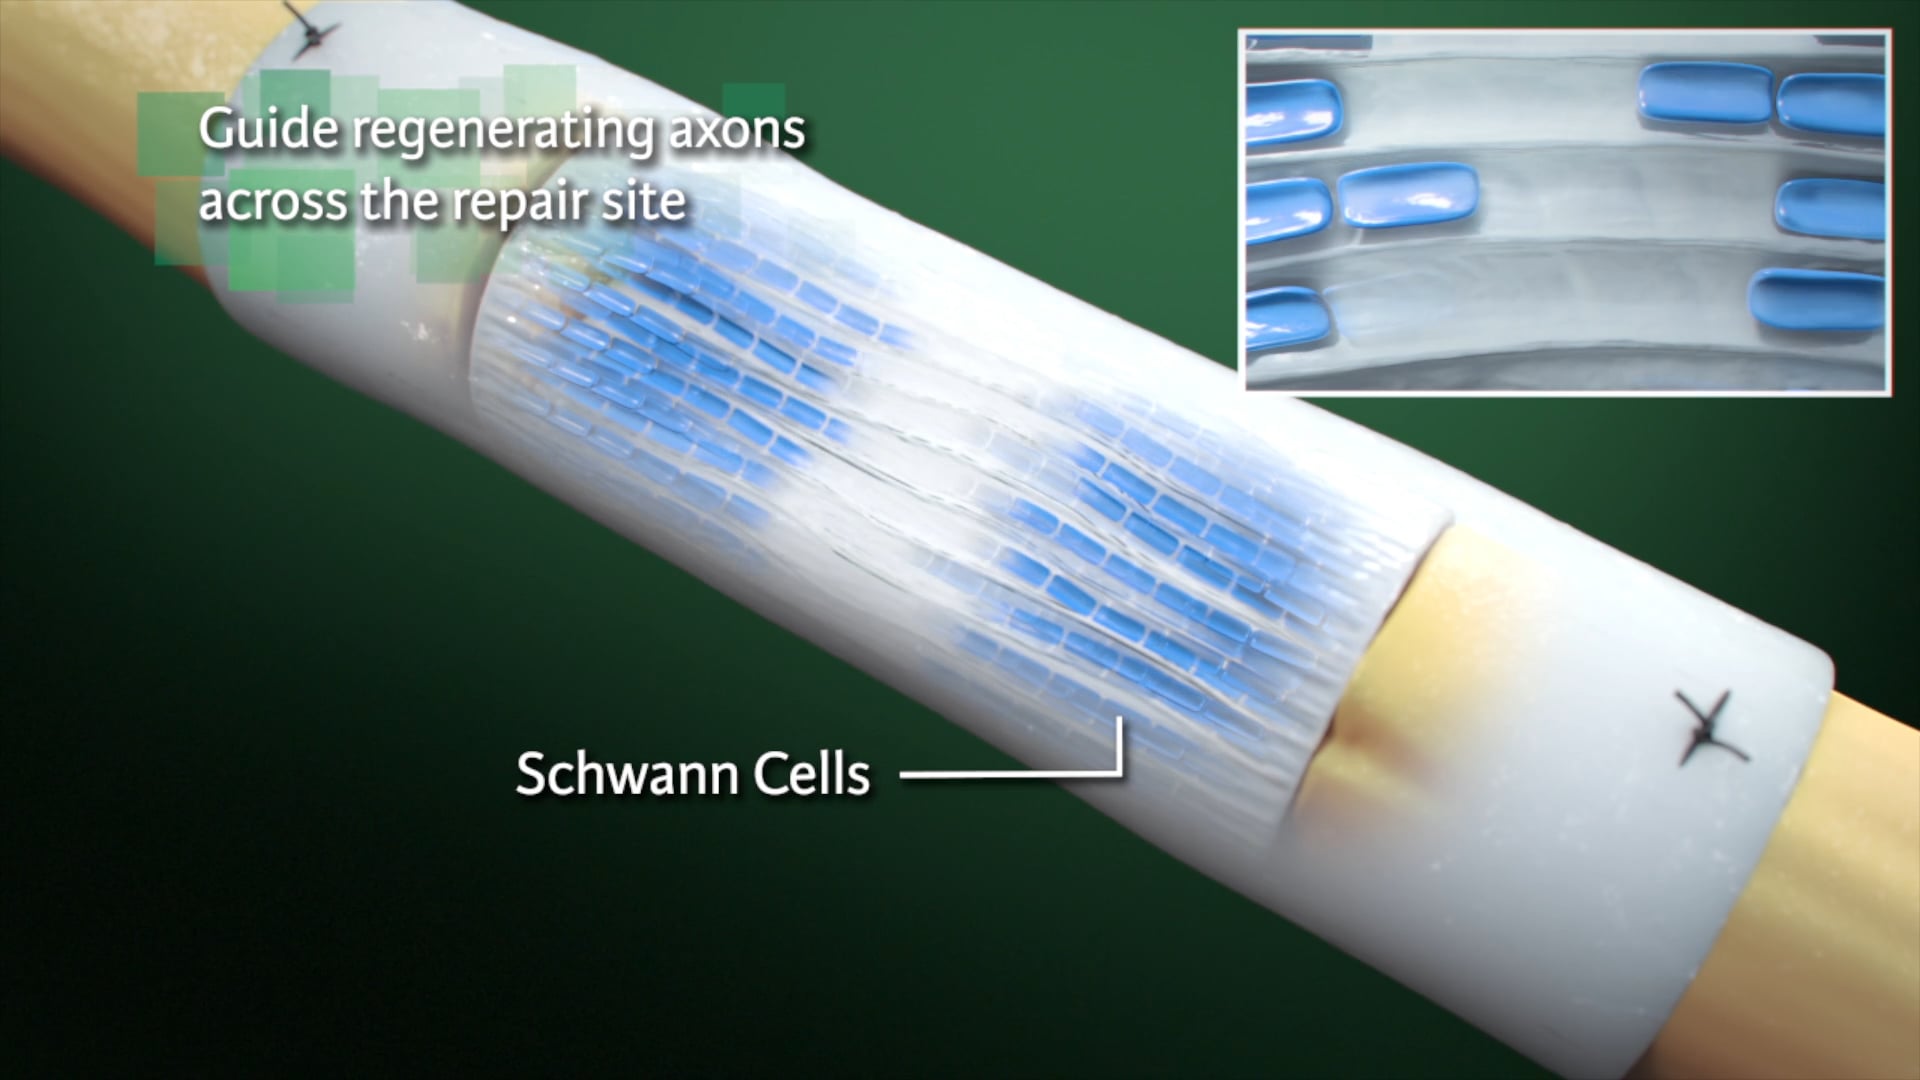

Medical Animation

Neurology